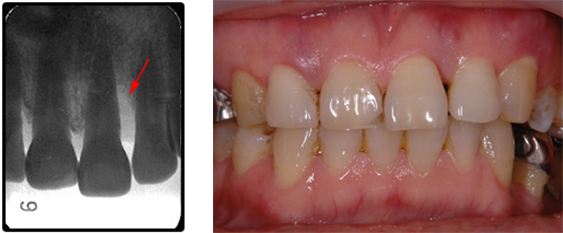

写真は、歯並びの不整とアンバランスな歯と歯茎のラインや歯の長さを改善するため、矯正治療の後に不揃いな歯茎を切除し形態を自然な歯の長さに回復した状態です。

BEFORE(初診時)

この症例では、歯間部の歯槽骨は骨吸収によって失われ、3mm程度の浅い骨縁下欠損を認めました(矢印)。

歯と歯の間の骨が無くなっているのが解りますか?

見た目には解りにくいですが歯茎から膿が出て腫れています。

AFTER ( 術中・術後 )

エムドゲインを使用し歯と歯の間の垂直的硬組織の再生に成功したケースです。

術中である左の写真で、無くなっていた歯と歯の間の骨が再生しかけているのがおわかりいただけるでしょうか?

向かって右の術後の写真では完全に再生されました。

術後6年経過した現在も、膿漏の再発も無く予後は安定しています。